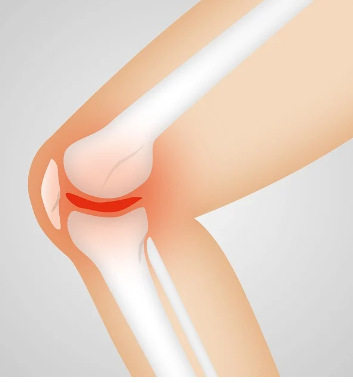

무릎 통증: 슬개골연골연화증 환자들은 운동 후 또는 계단을 오를 때 주로 통증을 느끼며, 이는 질환의 전형적인 증상입니다.

부종: 슬개골연골연화증으로 인해 무릎이 부풀어 오를 수 있습니다.